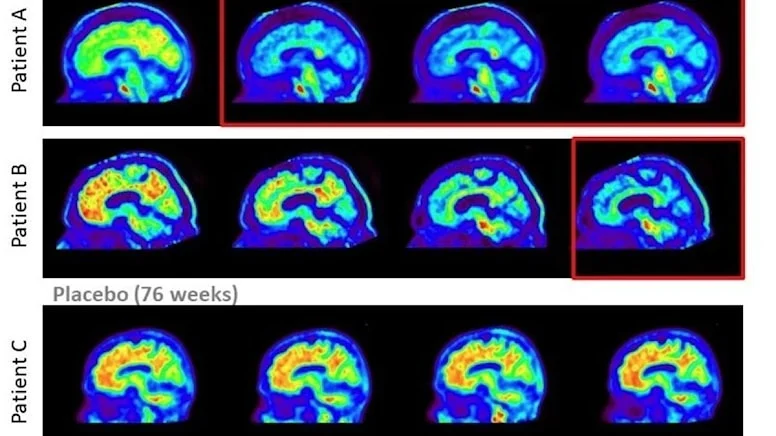

Alzheimer hastalığında yeni umut: Hastalığı yavaşlatmayı başardılar -

Yaşlanma tarihe karışabilir -